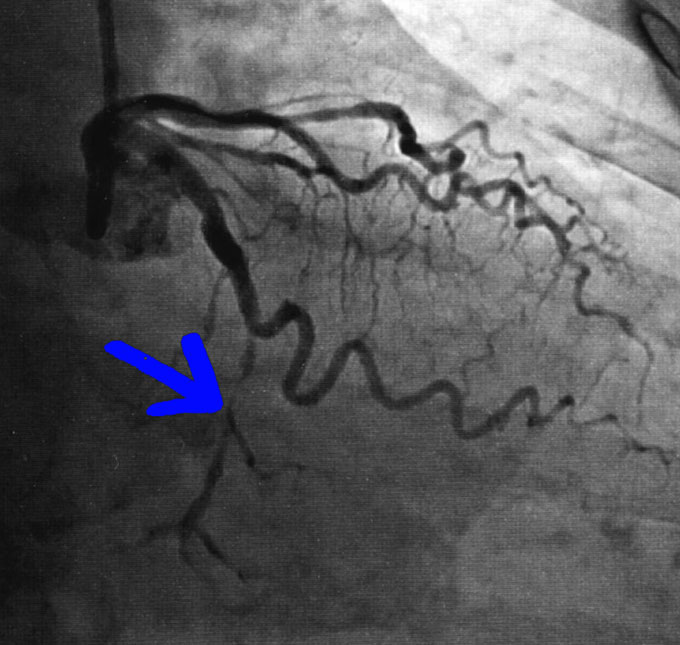

これが、手術前の血管。矢印の部分が狭くなっていますね。

そこにステントを入れた(青いマーカーの横)ので、こんなに血管が広がりました。

執刀医は「100パーセント成功です」と言ってくれましたね。